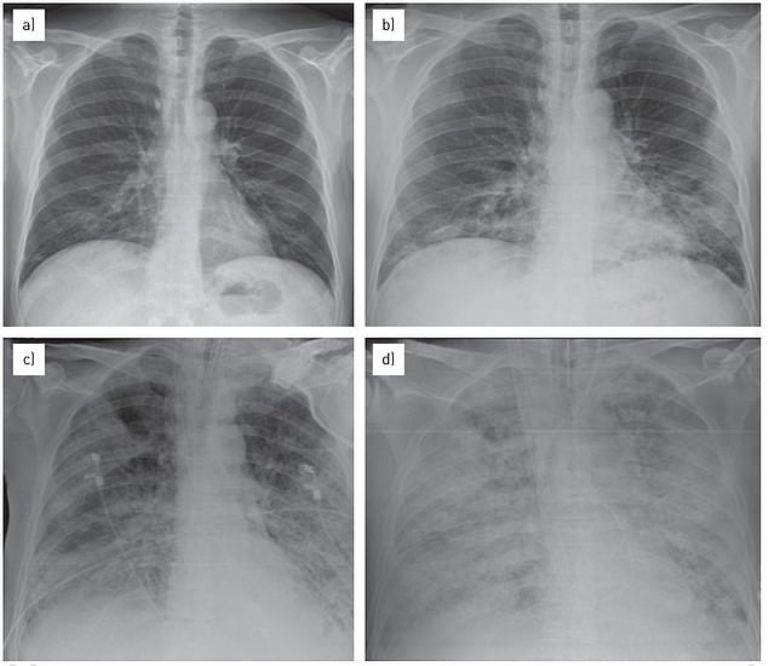

Massachusetts, Estados Unidos. - Los profesionales de la salud en partes de Massachusetts y Ohio han reportado un alarmante aumento en los casos de neumonía infantil, denominada "síndrome del pulmón blanco", similar a un brote que se está propagando en China y partes de Europa.

En el oeste de Massachusetts, médicos han observado un aumento significativo en la "neumonía ambulante", una forma más leve de esta enfermedad pulmonar.

En el condado de Warren, los pacientes, en su mayoría de ocho años de edad, han dado positivo por Mycoplasma pneumoniae, adenovirus y estreptococos. Por otro lado, en Massachusetts, el virus respiratorio sincitial (VRS) ha sido identificado como un problema principal.